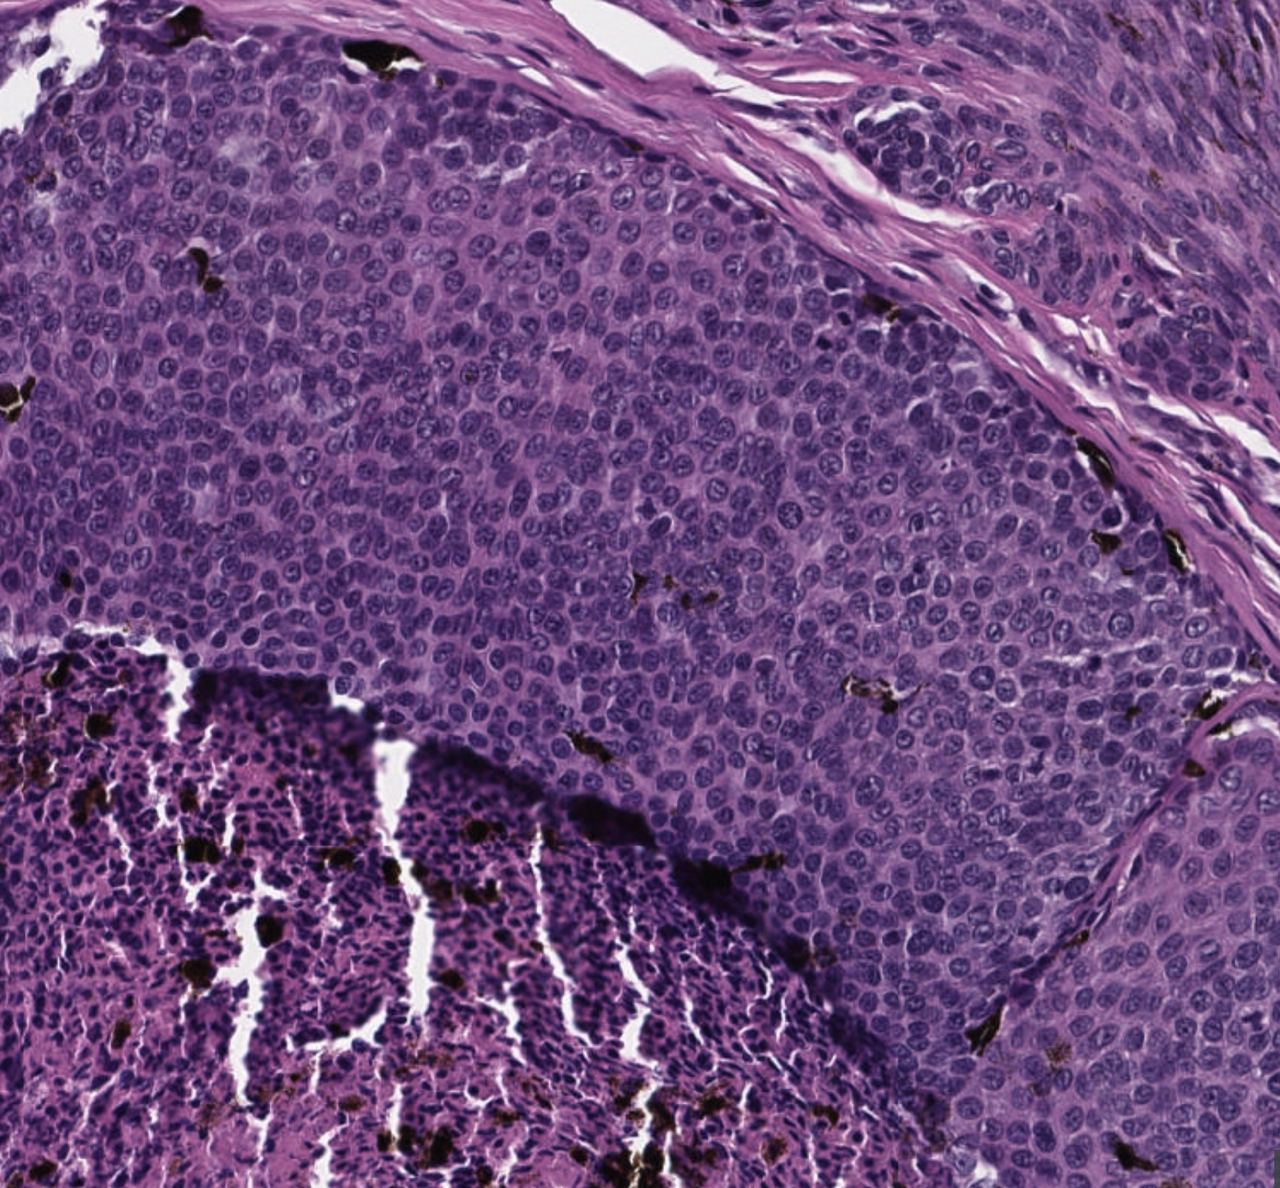

Редкая нынче находка, особенно в гистологических препаратах. Клещи рода Demodex

Базально - клеточная опухоль